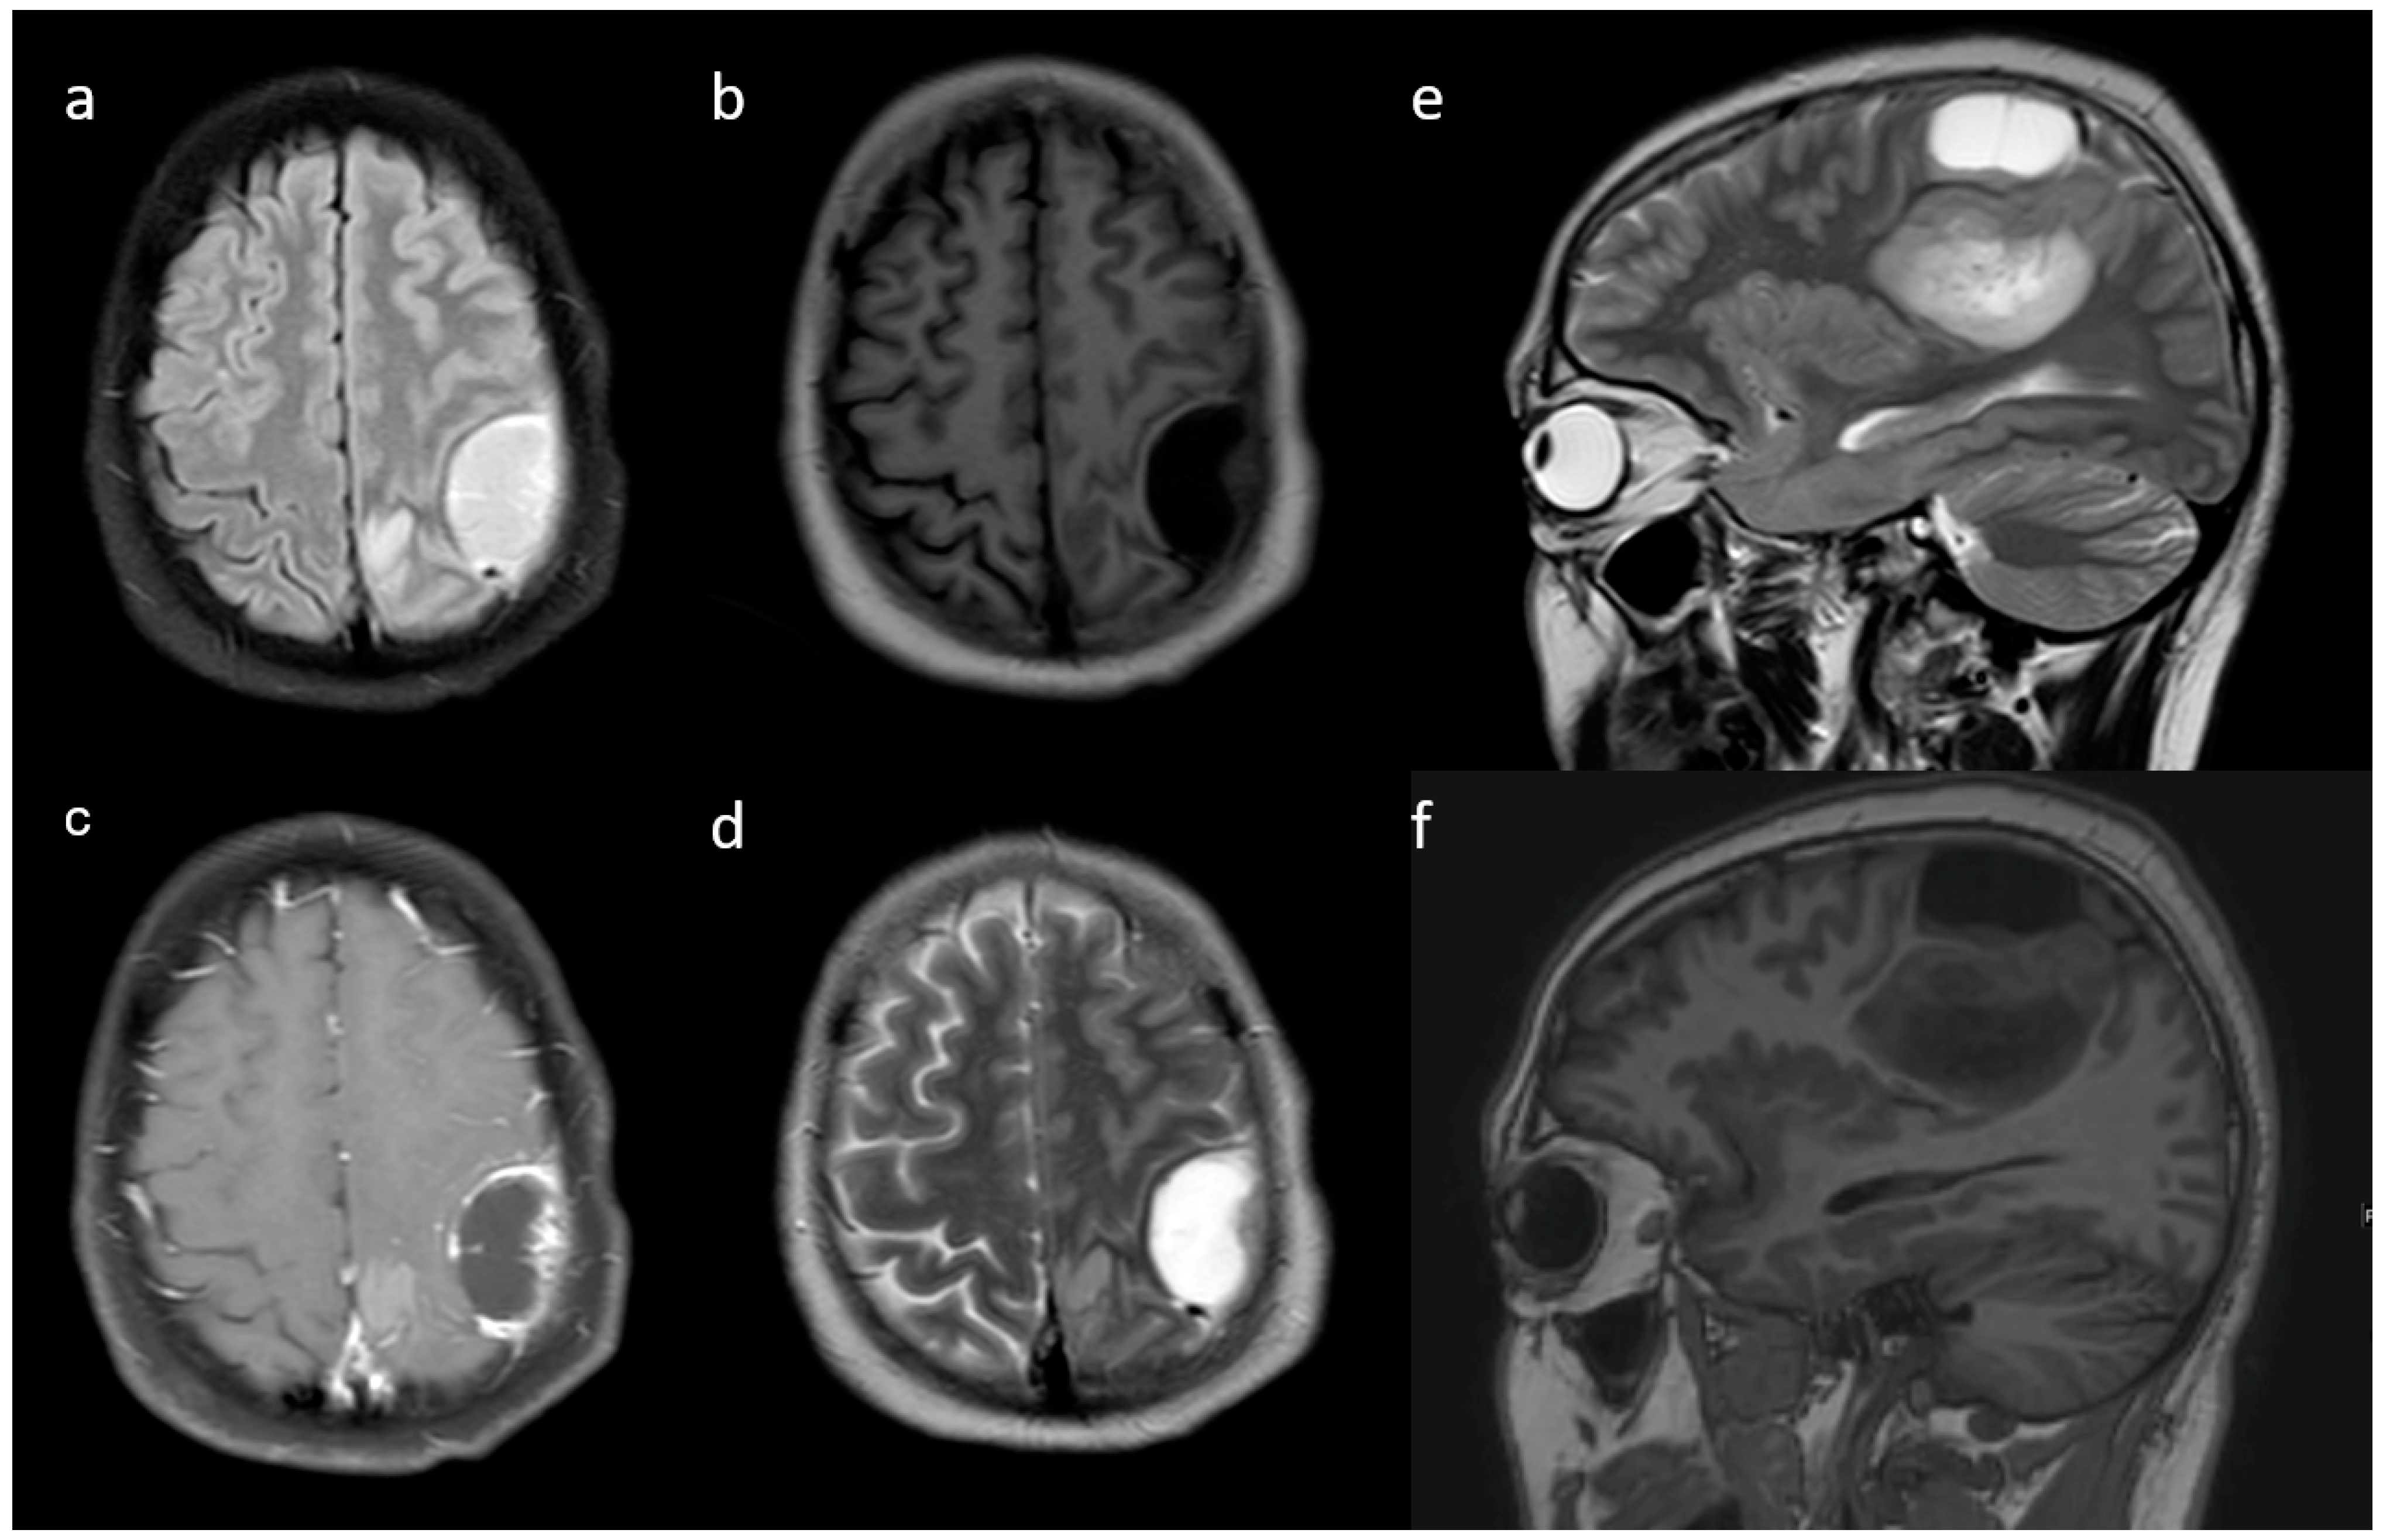

| Cysts * | No | 11 (57.9) | 115 (89.1) | 0.001 |

| Yes | 6 (31.6) | 14 (10.9) | ||

| Subcortical involvement | Involved | 18 (94.7) | 94 (72.9) | 0.044 |

| Not involved | 1 (5.3) | 35 (27.1) | ||